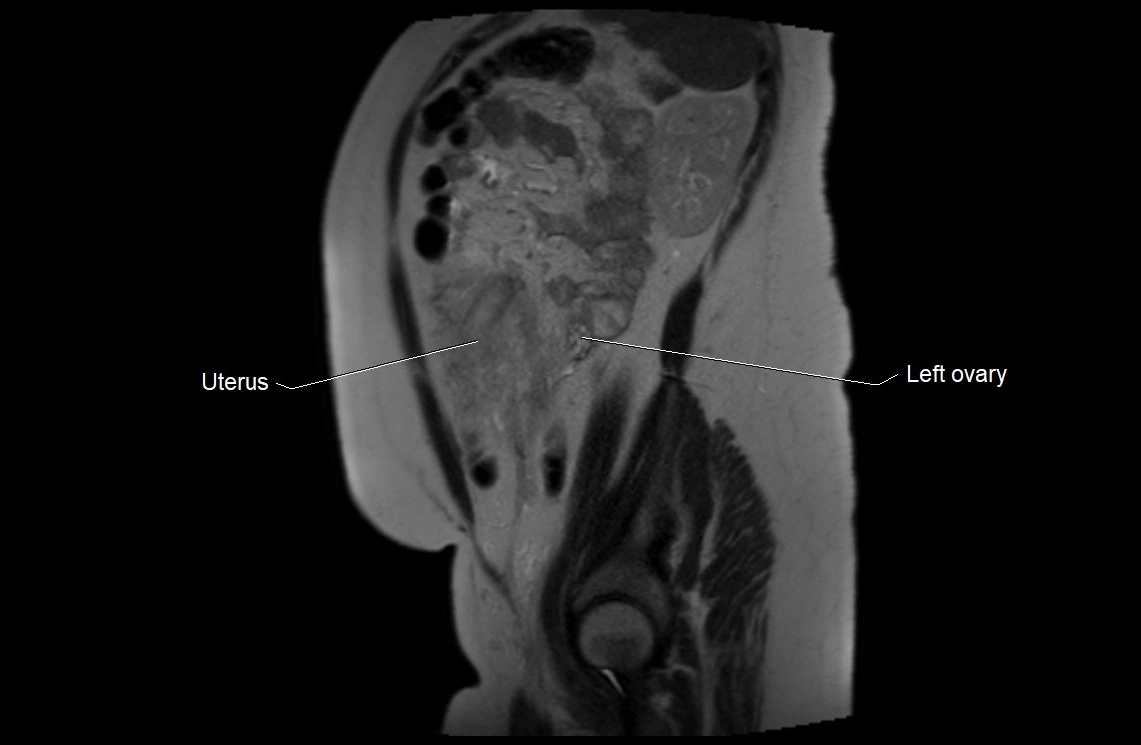

MRI Appearance

T2 HASTE (T2 GRE):

• Amniotic fluid shows very bright hyperintense signal

• Provides natural contrast against fetus and placenta

• Small particles (vernix) may appear as scattered hypointense foci within bright fluid

T1 GRE:

• Amniotic fluid shows low signal intensity (dark)

• Hemorrhage, infection, or proteinaceous content may cause focal or diffuse high signal intensity